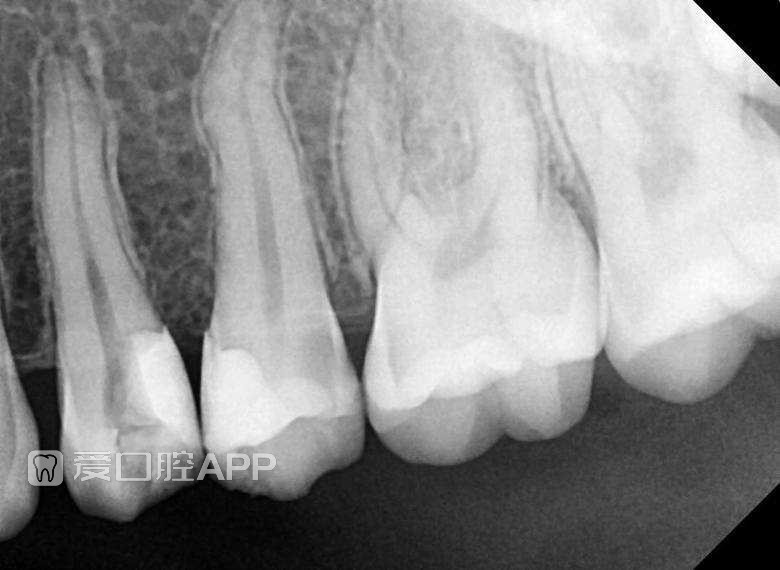

看个补牙 —— 上颌456